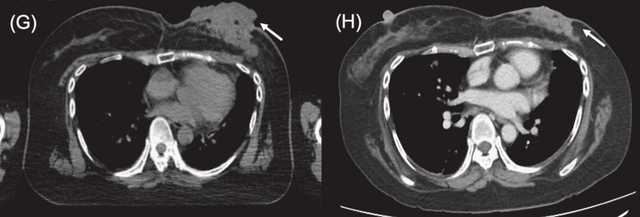

病例3

一名76岁女性,患有三阴性浸润性导管癌。其后出现胸壁和腋窝复发,侵犯臂丛神经并导致右臂完全瘫痪。BNCT治疗后右肩部和皮下病灶消退,仅残留小腋窝结节,2025年11月的随访胸部CT显示,患者照射部位保持部分缓解,局部控制得到改善。